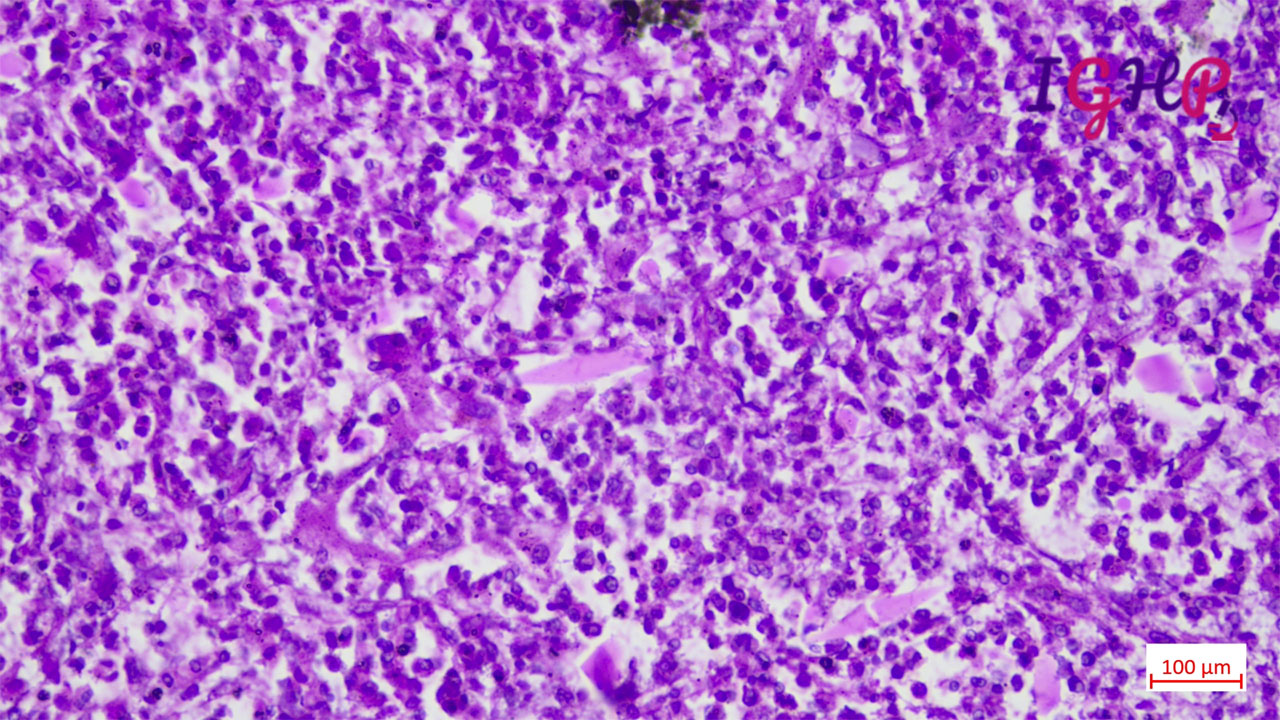

Microscopic Images-

Microscopic examination showed eosinophilic abscess with multiple cholesterol clefts.

PAS, MT and Orcein stains performed showed presence of CharcotLayden crystals.

Visceral larva migrans (VLM) is a parasitic (roundworm) infestation caused by Toxocaracanis and Toxocaracati of the genus Toxocara.Liver biopsy is characterized by eosinophilic granulomas and the presence of Charcot-Leyden crystals, which are formed from the breakdown of eosinophils.